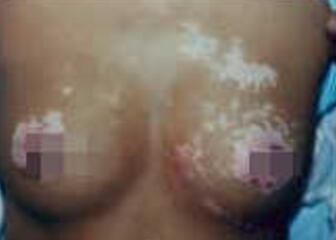

【小孩胸部患白癜风怎么办】随着现今科学技术的发展,白癜风的治好已不再是渴望,一些白癜风患者总是抱怨自己治疗没什么效果,主要是患者发现的不及时,治疗又不按章法了,所以导致后病情恶化,难以治好的后果。下面有成都博润白癜风医院医生为大家讲解。

白癜风之所以是难以治疗,用药没有效果,很大的程度上就是患者的病因没有找到,随便的进行用药的。白癜风虽然只是一种疾病,但是这个奇怪就在于,白癜风的病因是比较复杂的。所以,在对于孩子的白斑进行治疗,是应该带孩子到专业的白癜风医院去,检查,去找到白癜风的发病原因,这样才能让这个白斑的治疗是有效果的。推荐阅读:胸部白癜风要吃那些水果